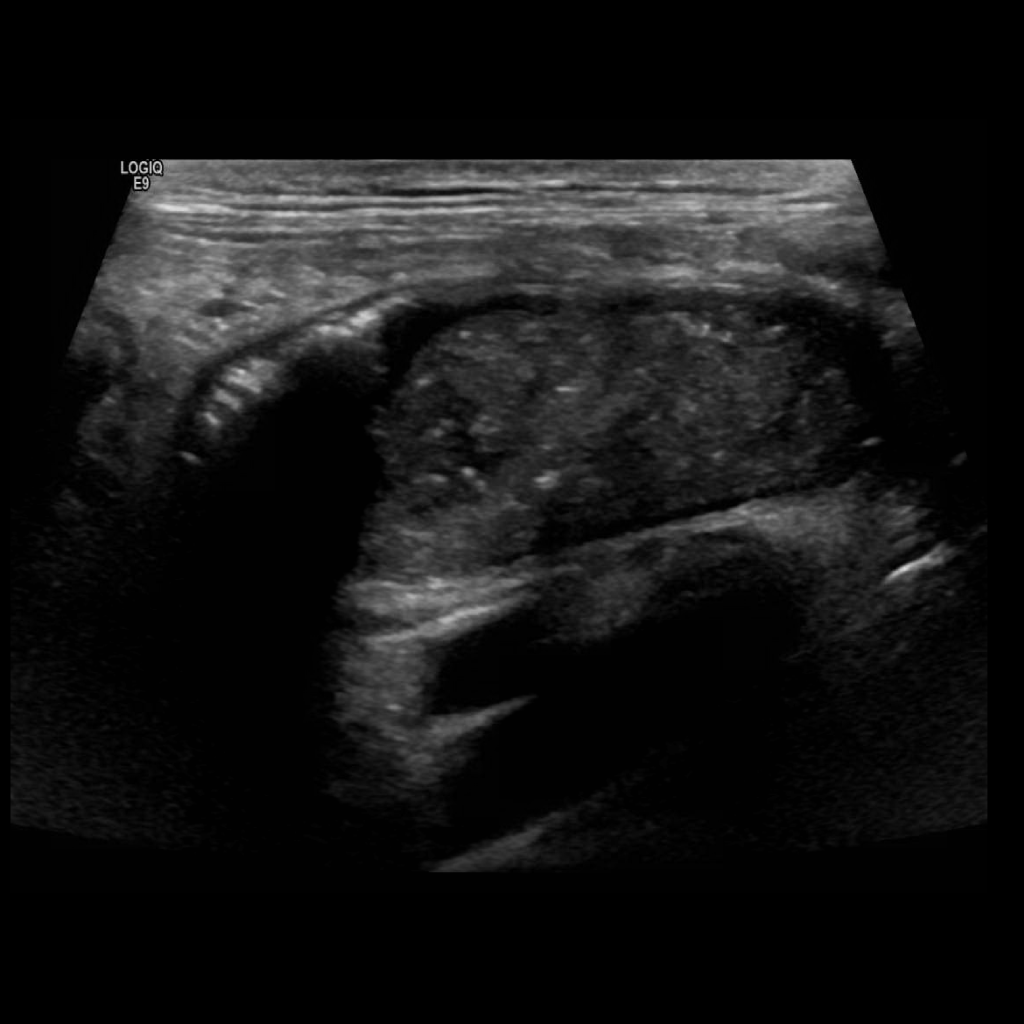

Appendicitis 4

1 cm appendicitis with hyperemia and appendicolith